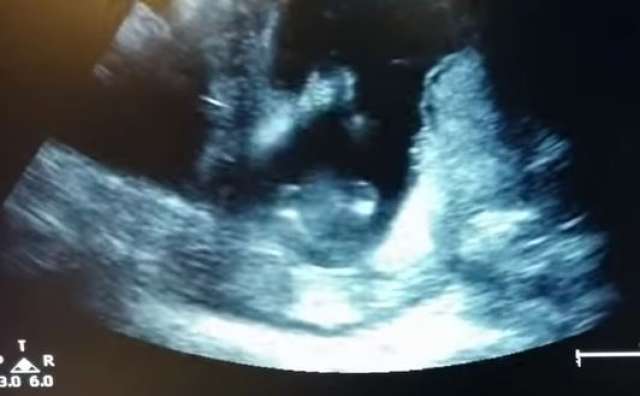

توجهت سيدة حامل في شهرها الثالث مع زوجها لرؤية طفلهما عبر "السونار".

واندهش الوالدان كثيرًا عندما كانا يرددان الأغنية الشهيرة "Happy"، ووجدوا الطفل يصفق بكفيه على أنغام الأغنية داخل رحم الأم، وكأنه يسمعهما أو يفعل ما تقوله الأغنية، ذلك وفقًا لما ذكره موقع "مترو" البريطاني.